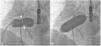

There was a small right-to-left shunt through the 2.3 mm wide fenestration between the lateral tunnel and the left atrium (Figure 1). The catheter was passed into the left atrium through the fenestration. The mean left atrial pressure was measured at 15 mmHg. Intraprocedural transesophageal echocardiography (TEE) revealed a restrictive ASD about 3 mm in diameter with a peak flow velocity of 2.2 m/s (pressure gradient of about 20 mmHg) across it. A guide wire was then advanced from the left atrium across the ASD into the right atrium. The mean right atrial pressure was 11 mmHg. Next, a snare catheter was passed into the aorta via the right femoral artery, and advanced into the right ventricle and the right atrium. The guide wire in the right atrium was grasped by the snare catheter, thus creating an arteriovenous loop. A 20 mm × 45 mm balloon catheter (Balton, Warsaw, Poland) was subsequently inserted over this arteriovenous loop and the balloon was inflated within the ASD. However, the balloon ruptured while fully inflated. The widened ASD now measured about 6 mm in diameter. There was a peak flow velocity of 1.6 m/s (pressure gradient of about 10 mmHg) across the defect as demonstrated by TEE. This result was deemed unsatisfactory and it was decided to repeat balloon dilation with a larger balloon. The catheter was again introduced and the guide wire was passed through the lateral tunnel, fenestration, left atrium, and the ASD into the right atrium. A 25 mm × 40 mm balloon catheter (Osypka AG, Rheinfelden-Herten, Germany) was advanced over the guide wire and positioned across the ASD (Figure 2A). The balloon was inflated until disappearance of the waist on the balloon (Figure 2B). After the septum was torn, the mean pressure gradient between the atria fell from 4 to 2 mmHg. TEE showed a final defect size of 11 mm with laminar flow across it (up to 1.2 m/s).